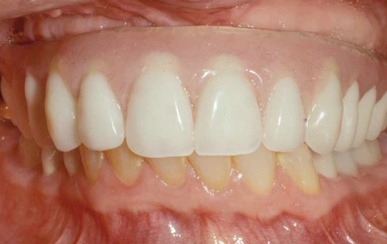

Fig 7. Existing dentition was sound periodontally and reasonably esthetic.

Figure 7

Interceptive implant therapy may then become a consideration earlier in life to create restorations that will not be subject to the latent effect of dental caries as aging continues. An example is shown in Figure 6 and Figure 7; the panoramic film of a 56-year-old man shows several orthognathic and extensive dental procedures historically. All full-coverage restorations had been replaced for a second time, and, again, all evidenced recurrent caries, but the existing dentition was periodontally sound and relatively esthetic.

Fig 6. Panoramic radiograph of 56-year-old patient illustrating a number of dental procedures historically.

Figure 6